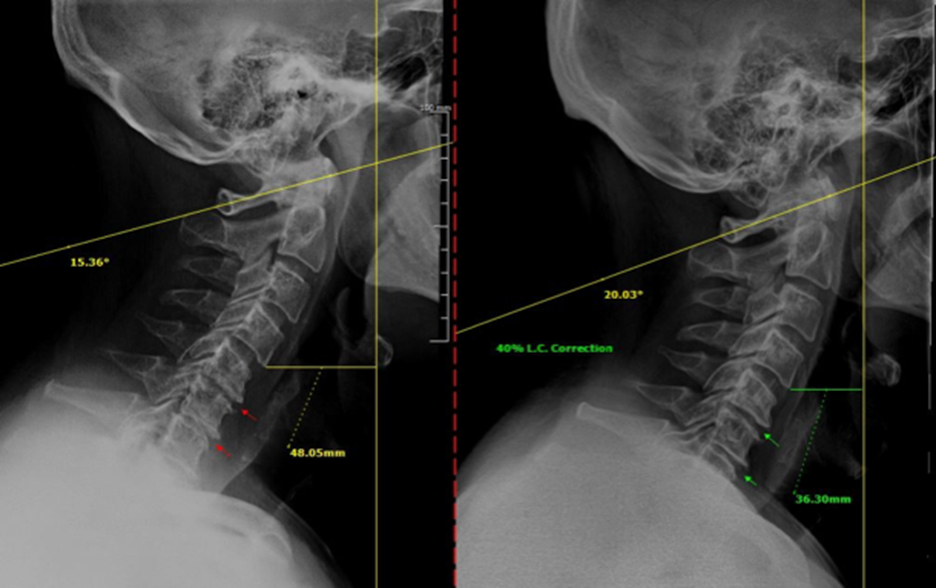

The x-ray changes above show the old x-ray on the left from January 2016 and the updated x-ray on the right from March of 2017. The left x-ray has the degeneration highlighted with red arrows between bones and the left has the improvement highlighted in those same areas with green arrows. There is also a measurement change in the front of the spine showing the 40% correction in spinal curvature of the neck.

A treatment plan was implemented, consisting of chiropractic adjustments and supportive therapies at a frequency of twice per week over four months. Reevaluation X-rays demonstrated a 40% correction in his cervical curve, along with increased disc spacing between two vertebral levels, indicating improved spinal alignment and function. Clinically, the patient experienced significant symptomatic relief, including reduced pain and tingling, as well as improved range of motion in his neck and shoulders. These changes allowed him to regain comfort and confidence in his daily activities.